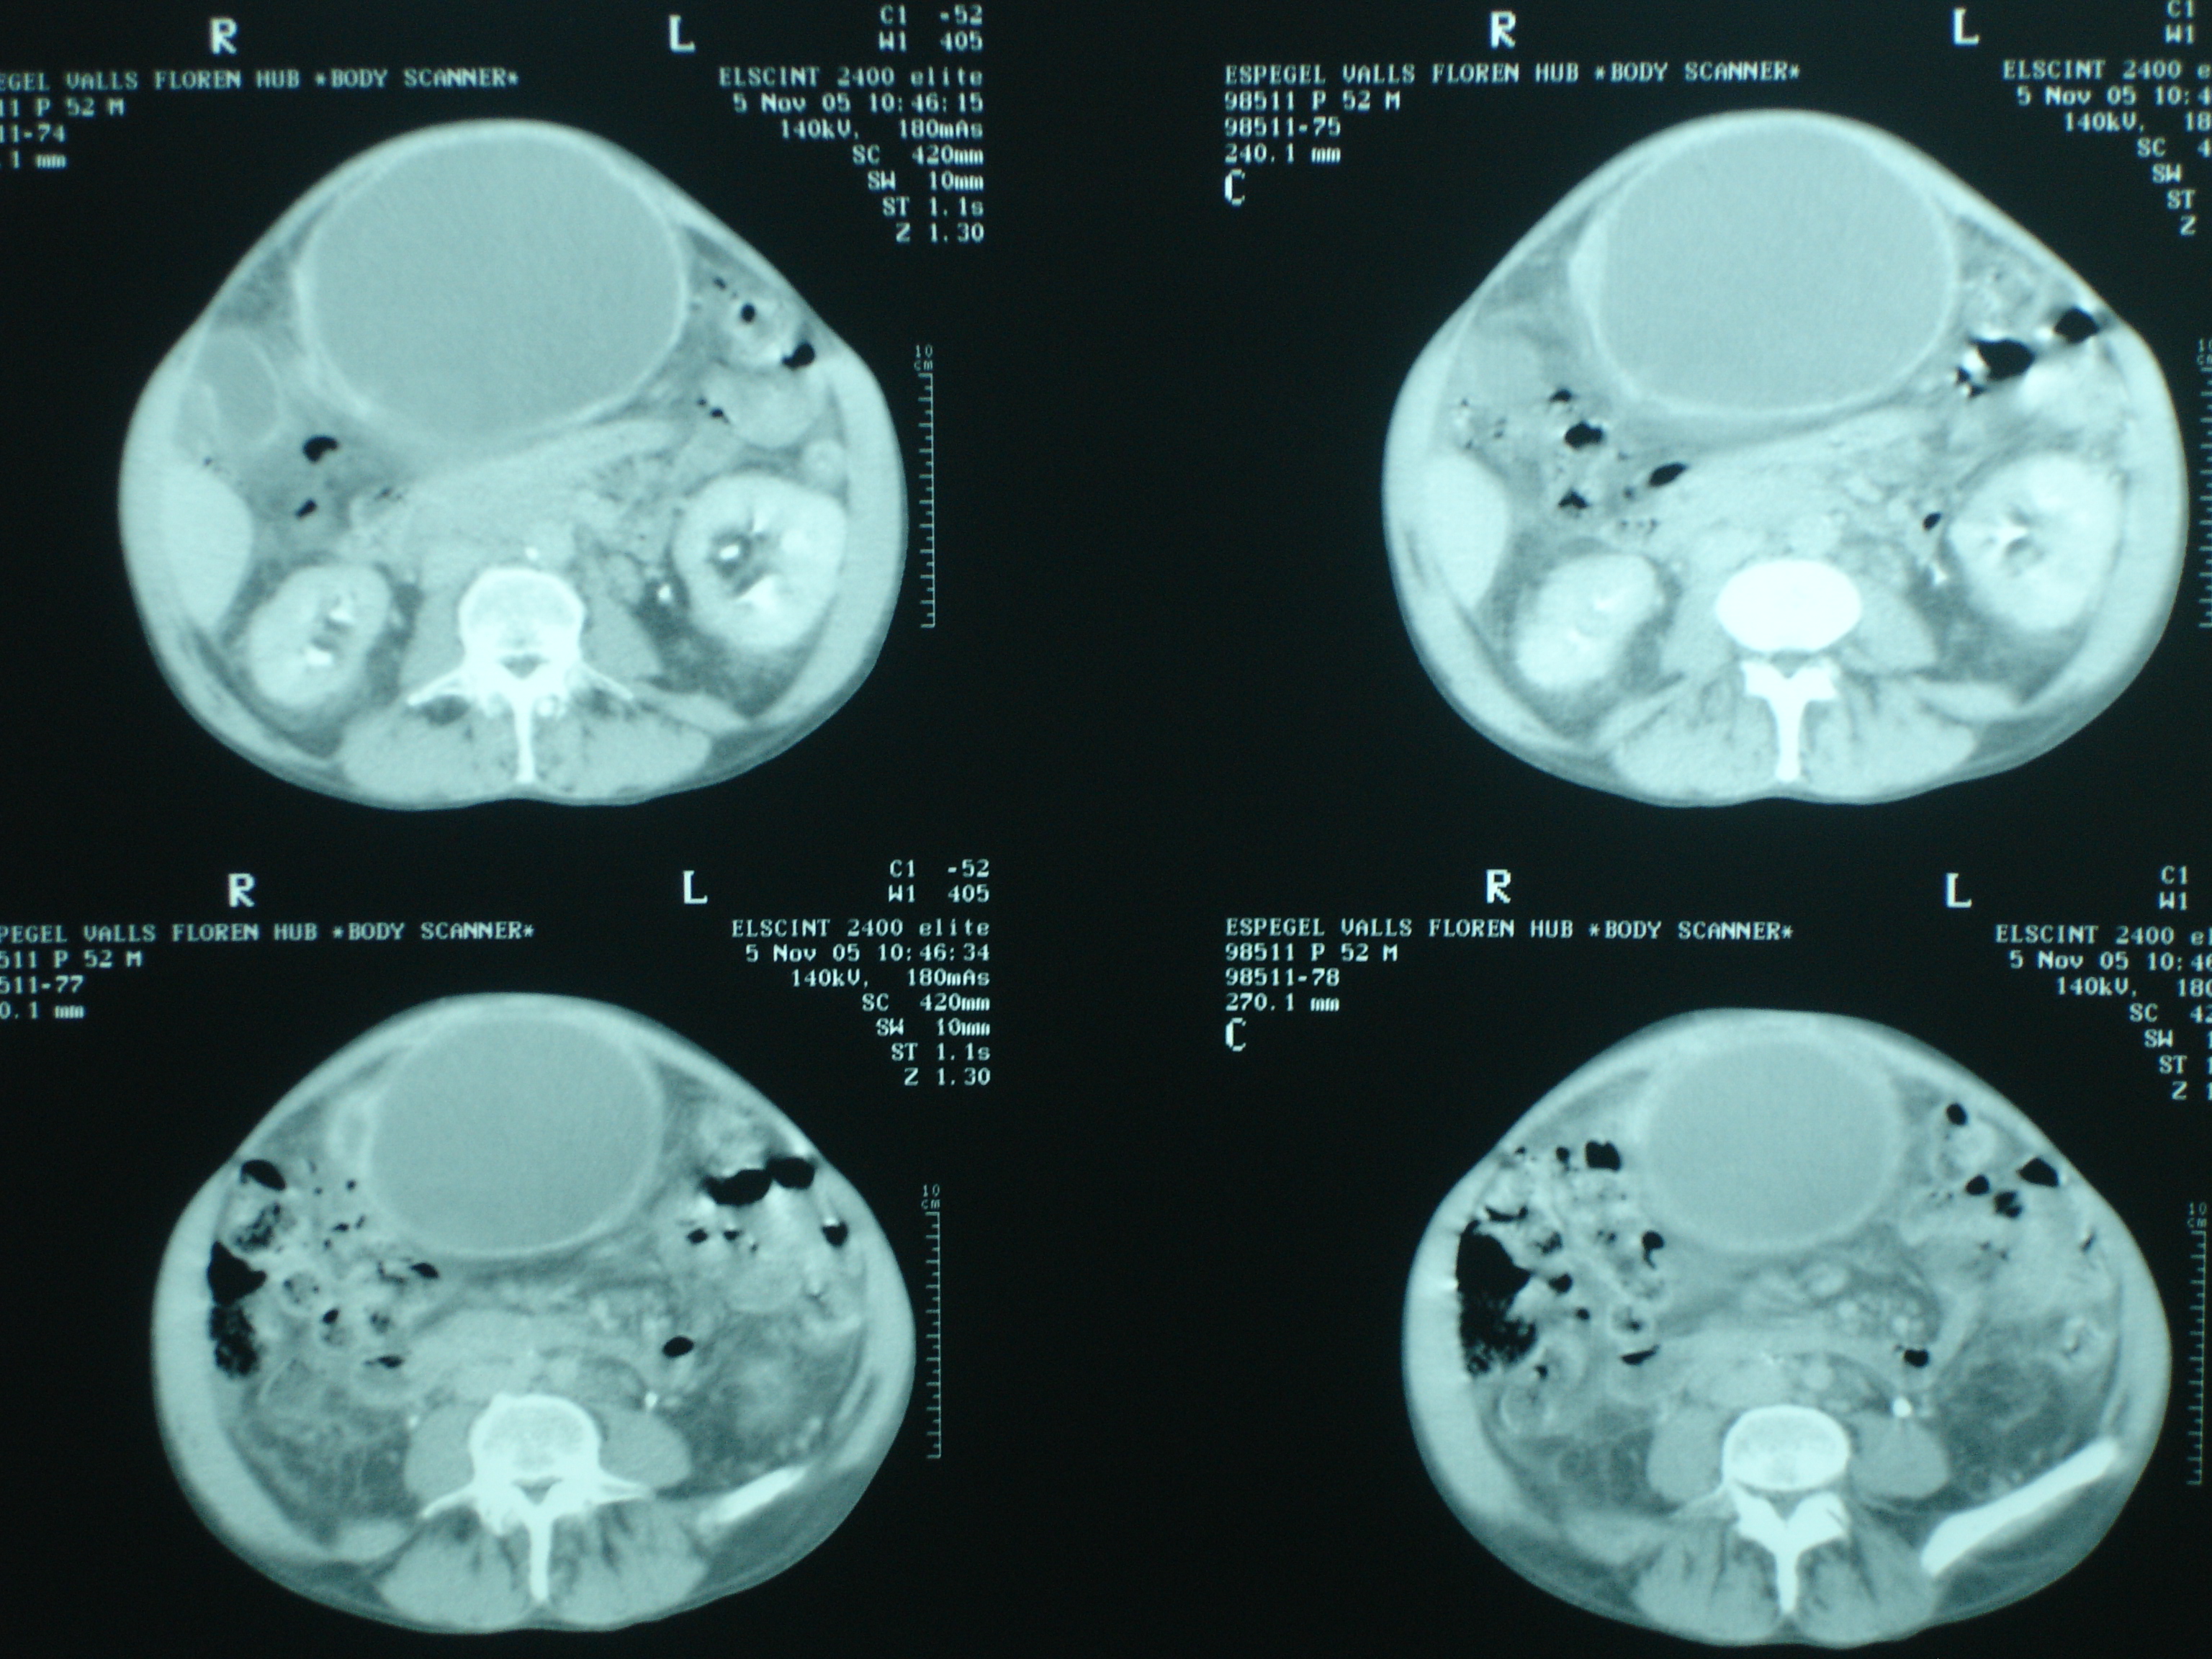

Imágenes de tomografía axial computerizada  de quistes hidatídicos hepáticos afectando segmentos V y VII, y con sustitución casi completa de los segmentos II y III